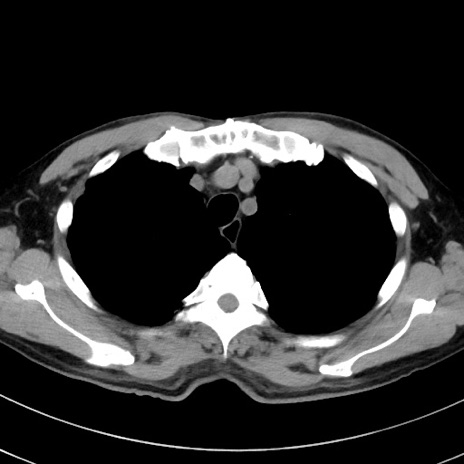

症例38(横断像)

【症例】70歳代 男性

【主訴】腹痛・嘔吐

【現病歴】昨晩より、嘔吐・腹痛あり。今朝になっても嘔吐あり。来院。

【既往歴】心臓バイパス手術、開腹胆摘、腸閉塞

【身体所見】BP 107/71mmHg、HR 116/min、腹部:平坦、軟、下腹部に軽度圧痛あり。反跳痛なし。

【データ】WBC 15100、CRP 0.32